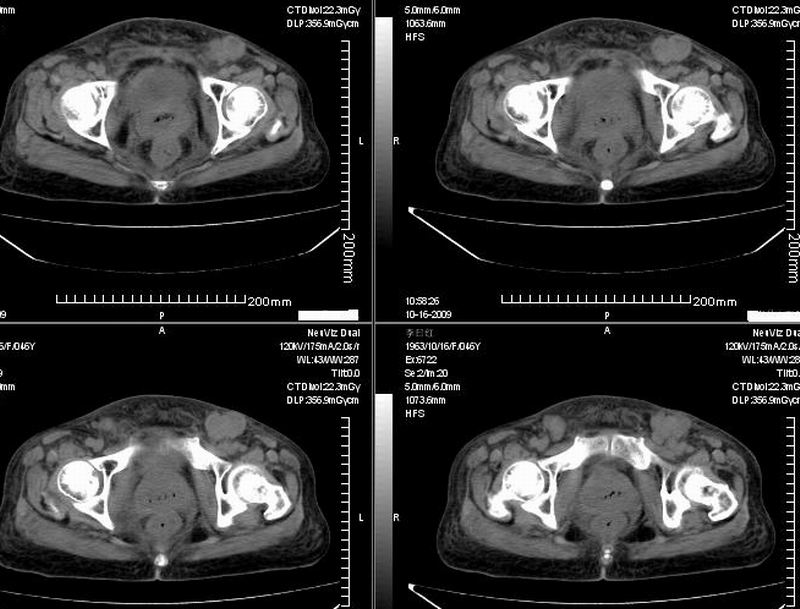

女:46y:一年前宫颈癌术后,现右下腹抚及肿块。

考虑宫颈癌术后复发周边侵犯/右中下腹及双侧腹股沟淋巴结转移。